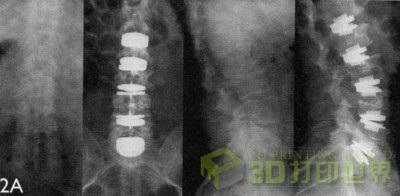

图4:“Lobster”垫块,通过影像技术显示,位于脊椎中。[图片来源:Concept Laser GmbH]

Stefano Caselli 将所谓的“Lobster”垫块描述成 Tsunami 的另一大创新。这是一种可以张开的垫块,可在脊椎重建手术中安放在两个椎间盘之间(图 3+4)。这种由 Tsunami 开发的张开机构是设计上的一个小奇迹:这是一个包含中央螺杆和侧方齿轮的传动机构,该机构可将两个翼片张开。使用 Concept Laser 的 Mlab cusing R 设备和 LaserCUSING 方法可以制造出表面完美配合的“Lobster”垫块。其低粗糙度 - 近乎光滑的表面 - 可以确保更少的组织增生。Stefano Caselli 认为这种制造工艺值得注意的地方在于:这种复杂活动部件的所有组件可以同时批量生产。“LaserCUSING 为我们提供了时间优势和成本结构优势,另外在无尘室制造的条件下,它明显比传统的制造方法更易于执行。除此之外, Concept Laser 的机器解决方案还具有优秀的性能和极高的安全水平,尤其是在对反应性材料,例如钛或钛合金进行加工时。”